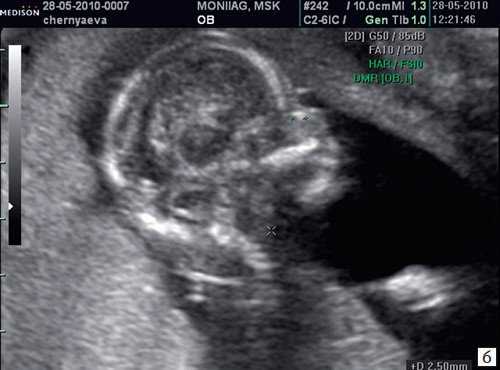

Копчико-теменной размер плода (КТР) для проведения скрининга I триместра должен быть в пределах 45-84 мм. Для оценки носовой кости в I триместре беременности необходимо соблюдать строгие условия. Это адекватное увеличение (на снимке должны быть только голова и верхняя часть грудной клетки), среднесагиттальный скан (должны быть визуализированы эхогенный кончик носа, небный отросток верхней челюсти, диэнцефалон), нос представлен тремя "К" (кончик носа, кожа, кость). Кожные покровы и кости носа визуализируются в виде знака "равенства", нос параллелен датчику.

Такие правила, как размер плода, адекватное увеличение, среднесагиттальный скан идентичны таковым при измерении ТВП. Таким образом, при выведении корректного скана для измерения ТВП, что является обязательным при проведении УЗ-исследования в сроки 11-14 нед беременности, оценка носовой кости проводится в том же самом срезе, не требуя получения дополнительных изображений.

Если все критерии соблюдены, то на уровне носа плода должны быть видны три четко различимые линии: верхняя линия представляет собой кожу, книзу от нее визуализируется более толстая и более эхогенная, чем кожа носовая кость. Третья линия, визуализируемая кпереди от носовой кости и на более высоком уровне, чем кожа - это кончик носа (рис. 1).

Рис. 1. Нормальная носовая кость.